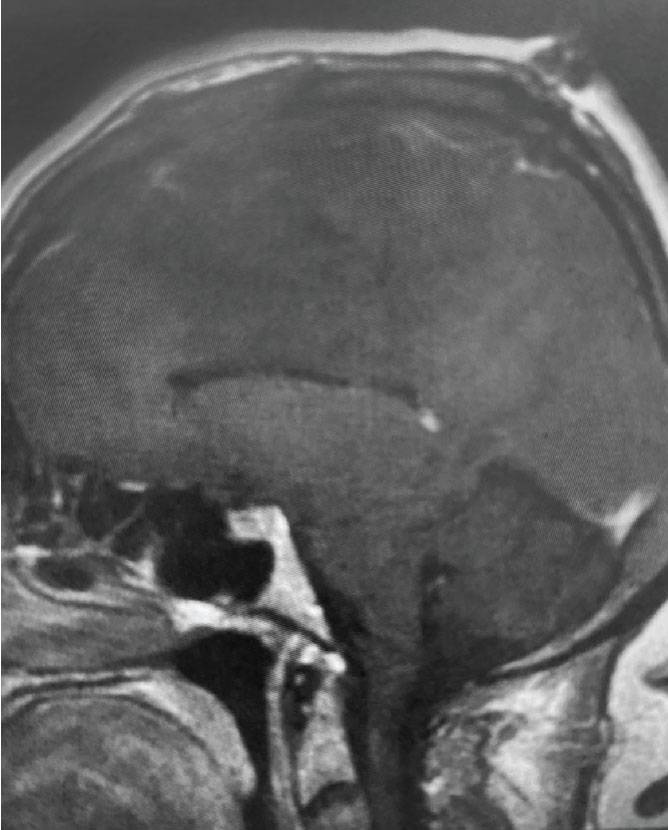

Fig 1. B) Pre-operative, sagittal post-contrast MRI.

This is a 55 year old right-handed woman who was having progressive balance problems. MRI with and without contrast demonstrated a 7 cm partly cystic meningioma involving the left frontal convexity and falx, and encasing the superior sagittal sinus. There was also tumor involvement of part of the convexity skull.

Convexity and Falx Meningiomas: While meningiomas can involve either the convexity or the falx alone, it is possible for such tumors to involve both structures. In this case, vascular supply to the tumor can originate from both dural sources. When meningiomas involve the convexity dura, the dura is often excised and replaced with a duraplasty (an artificial dural replacement). When tumors involve the falx, the falx itself is usually not removed in entirety.

Meningiomas that compress the motor strip: This meningioma was clearly compressing the left motor strip significantly, likely explaining the patient’s balance problems. That having been said, these tumors often have very distinct borders with the normal brain, and can be removed without harming the underlying motor strip.